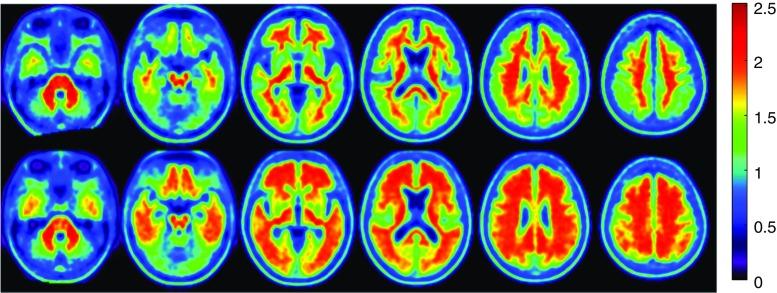

In this prospective study 66 participants with amnestic mild cognitive impairment underwent clinical, neuropsychological and PET amyloid imaging tests. Composite scores assessing memory and non-memory domains were used to identify two clinical classes of neuropsychological phenotypes expressing different degree of cognitive impairment. Detection of amyloid status and definition of optimal amyloid ± cutoff for discrimination relied on unsupervised k-means clustering method.

Threshold for identifying low and high amyloid retention groups was of SUVr = 1.3. Aß + participants showed poorer global cognitive and episodic memory performance than subjects with low amyloid deposition. Aß positivity significantly identified individuals with episodic memory impairment with a sensitivity and specificity of 80 and 79%, (χ2 = 21.48; P < 0.00001). Positive and negative predictive values were 82 and 76%, respectively. Amyloid deposition increased linearly as function of memory impairment with a rate of 0.13/ point of composite memory score (R = -44, P = 0.0003).

The amyloid burden of SUVr = 1.3 allows early identification of subjects with episodic memory impairment which might predict progression from MCI to Alzheimer's disease.